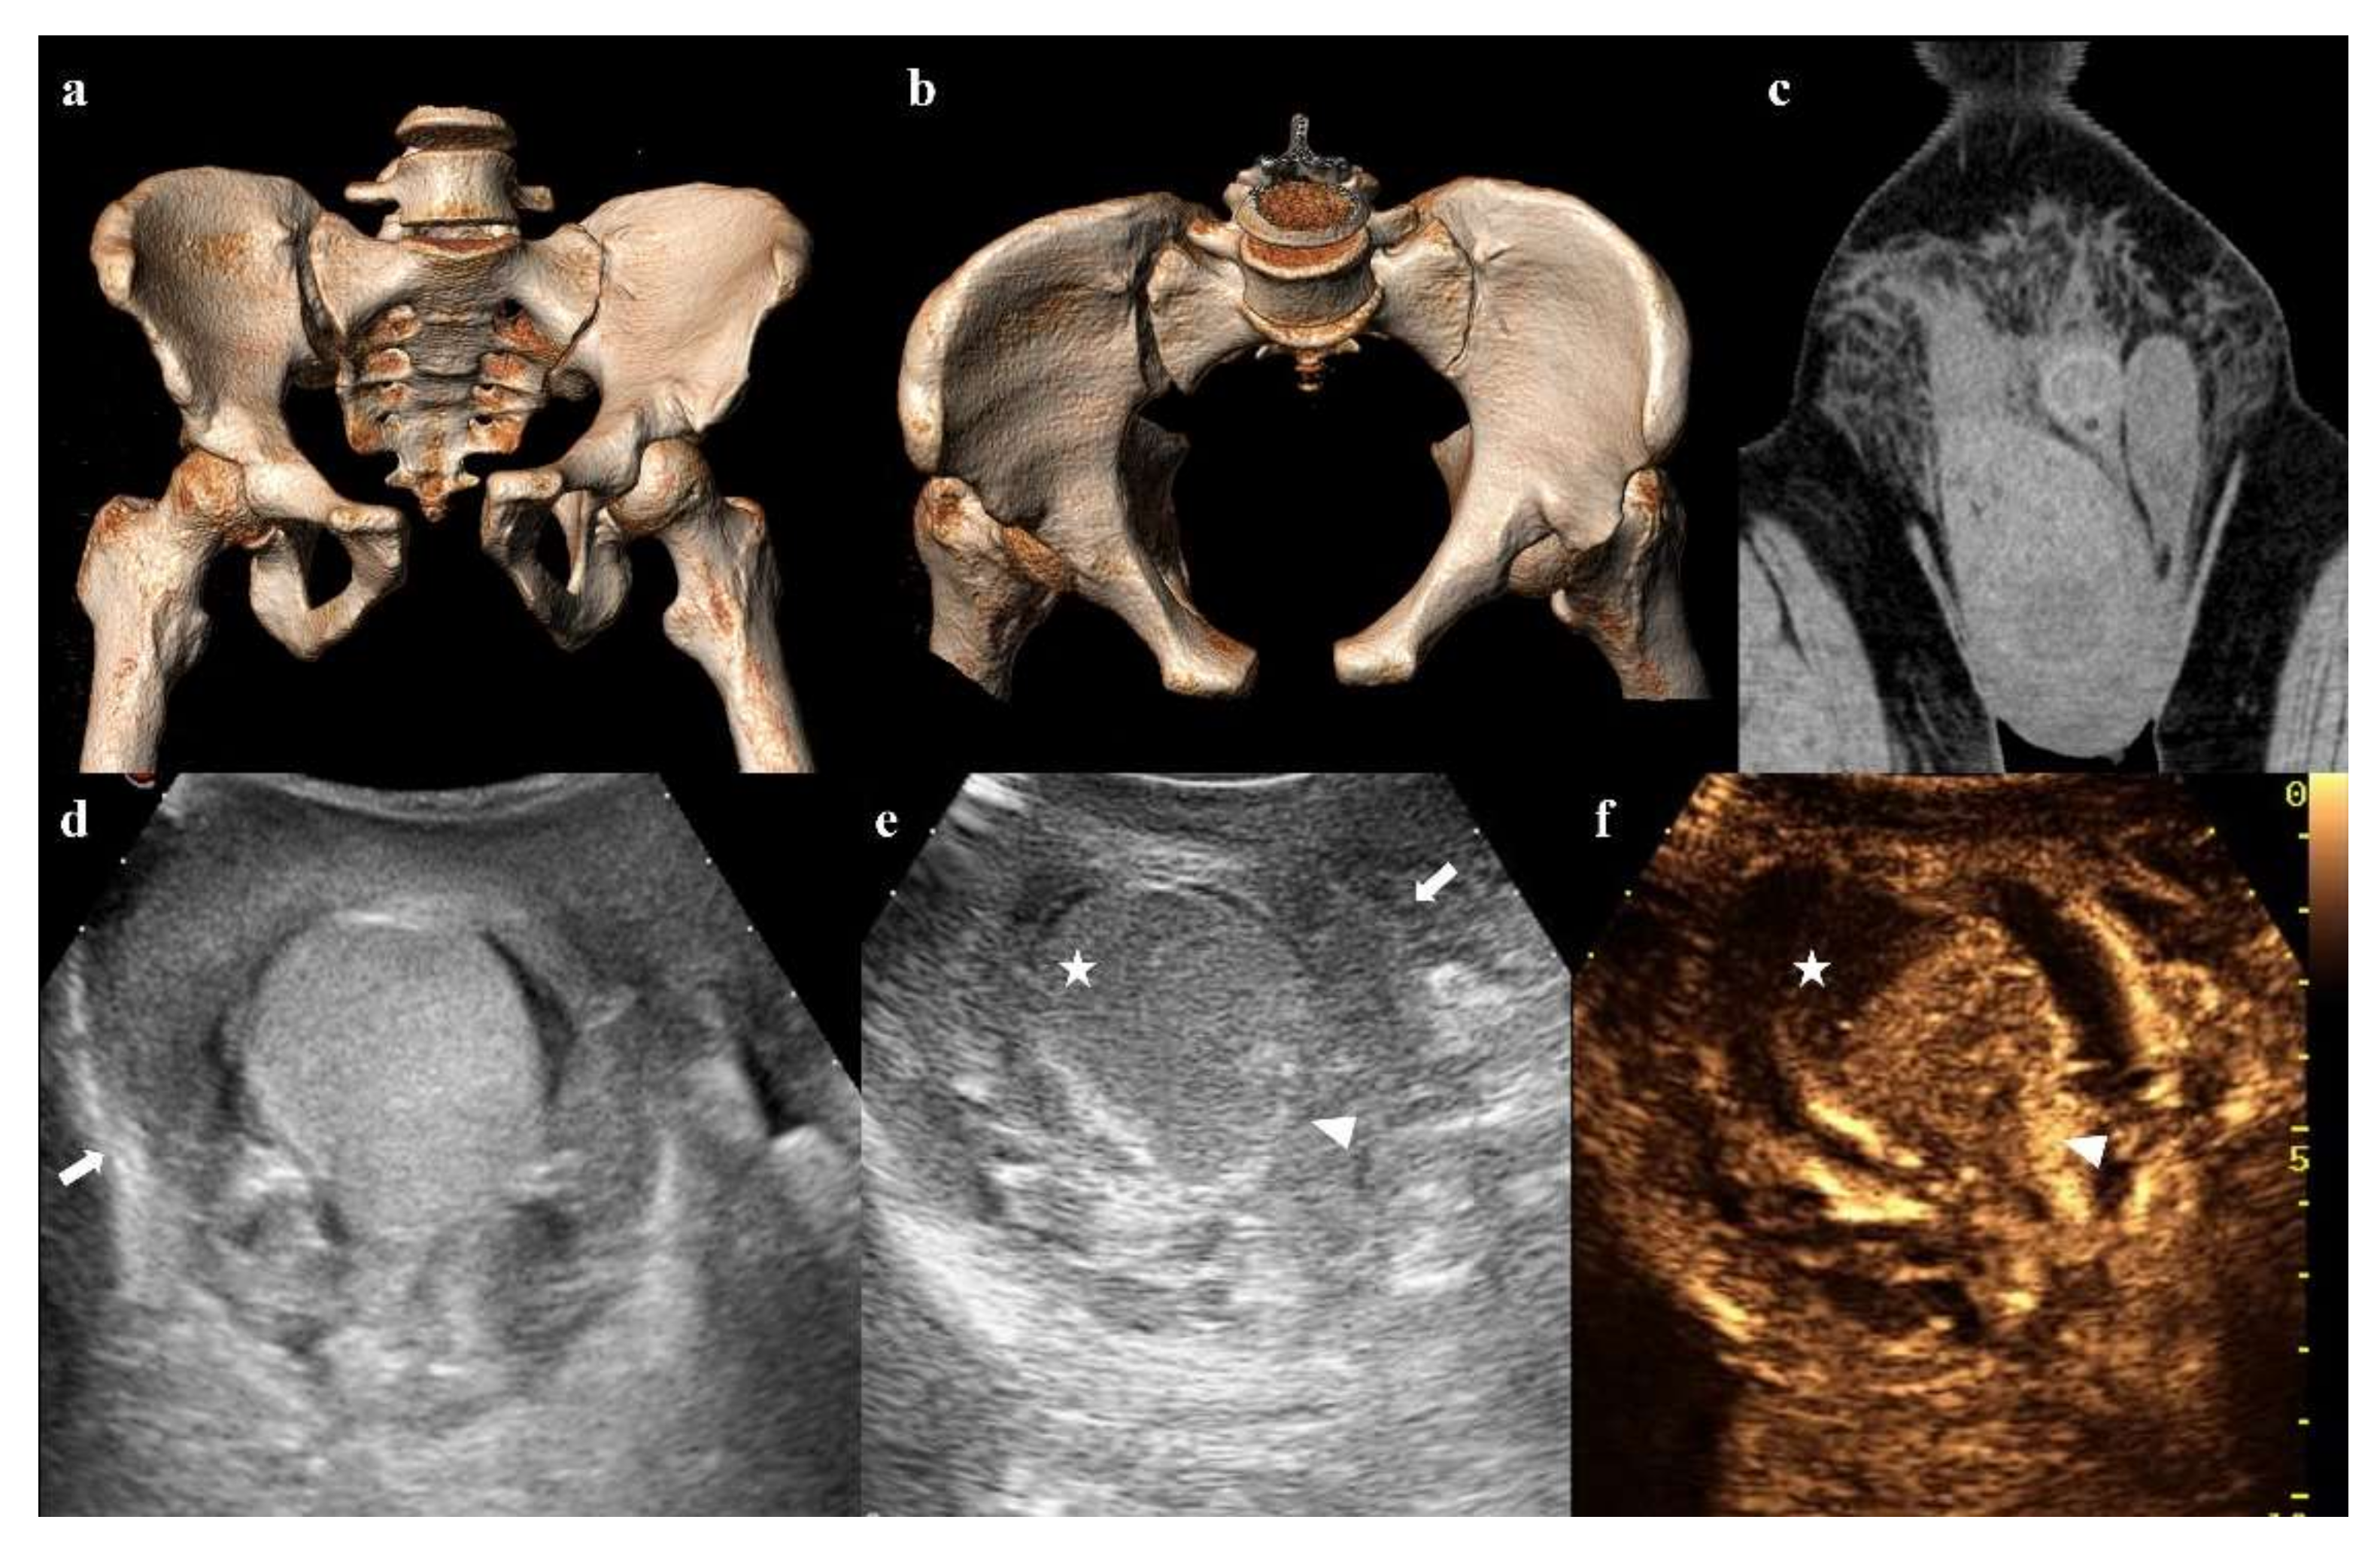

Testicular trauma can be associated with pelvic fractures, especially in the case of motor vehicle crashes and falls from a height [66].

Ultrasound and contrast-enhanced ultrasonography (CEUS) are indispensable in the proper management of these injuries. Findings of testicular trauma are hematocele, intratesticular hematoma, and testicular rupture (Figure 14) [67,68].

Magnetic resonance (MR) has great value in the evaluation of scrotal lesions, but it is rarely available in an emergency department [67,69]. Its use may be crucial in the identification of testicular rupture when ultrasound evaluation is inconclusive [70].

Figure 14. Three-dimensional volume-rendering CT reconstructions in AP and inlet views show an anterior–posterior compression fracture (a,b). Coronal CT image shows hematoma in the right inguinoscrotal region (c). Ultrasound shows an inhomogeneous hematoma on the extra-albuginea side (arrow in (d,e)) and a hypoechoic area in the upper part of the testis (star in (e)). Contrast-enhanced ultrasonography (CEUS) image clearly shows that the hypoechoic area is avascularized, as a hematoma (star in (f)). Ultrasound and CEUS also show the irregularity of the testicular contour (arrowhead in (e,f)). These findings are suggestive of testicular rupture.